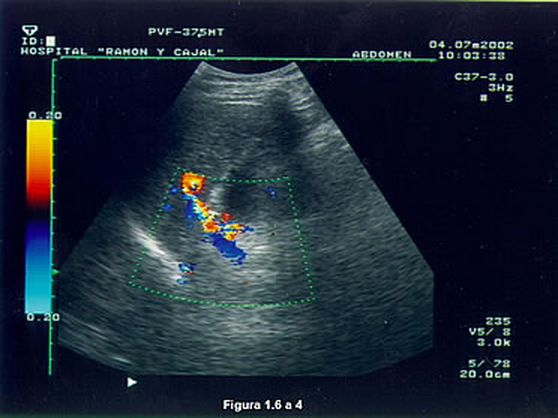

Trombosis y estenosis venosa La estenosis portal se localiza a nivel de la anastomosis quirúrgica. En modo B se sospecha el estrechamiento de calibre portal que se confirma mediante Doppler color y Angio Doppler. El Doppler pulsado muestra un aumento de la velocidad que puede ser 3-4 veces superior al de la porta pre-estenótica. A nivel post estenótico el flujo sanguíneo es rápido y turbulento. |